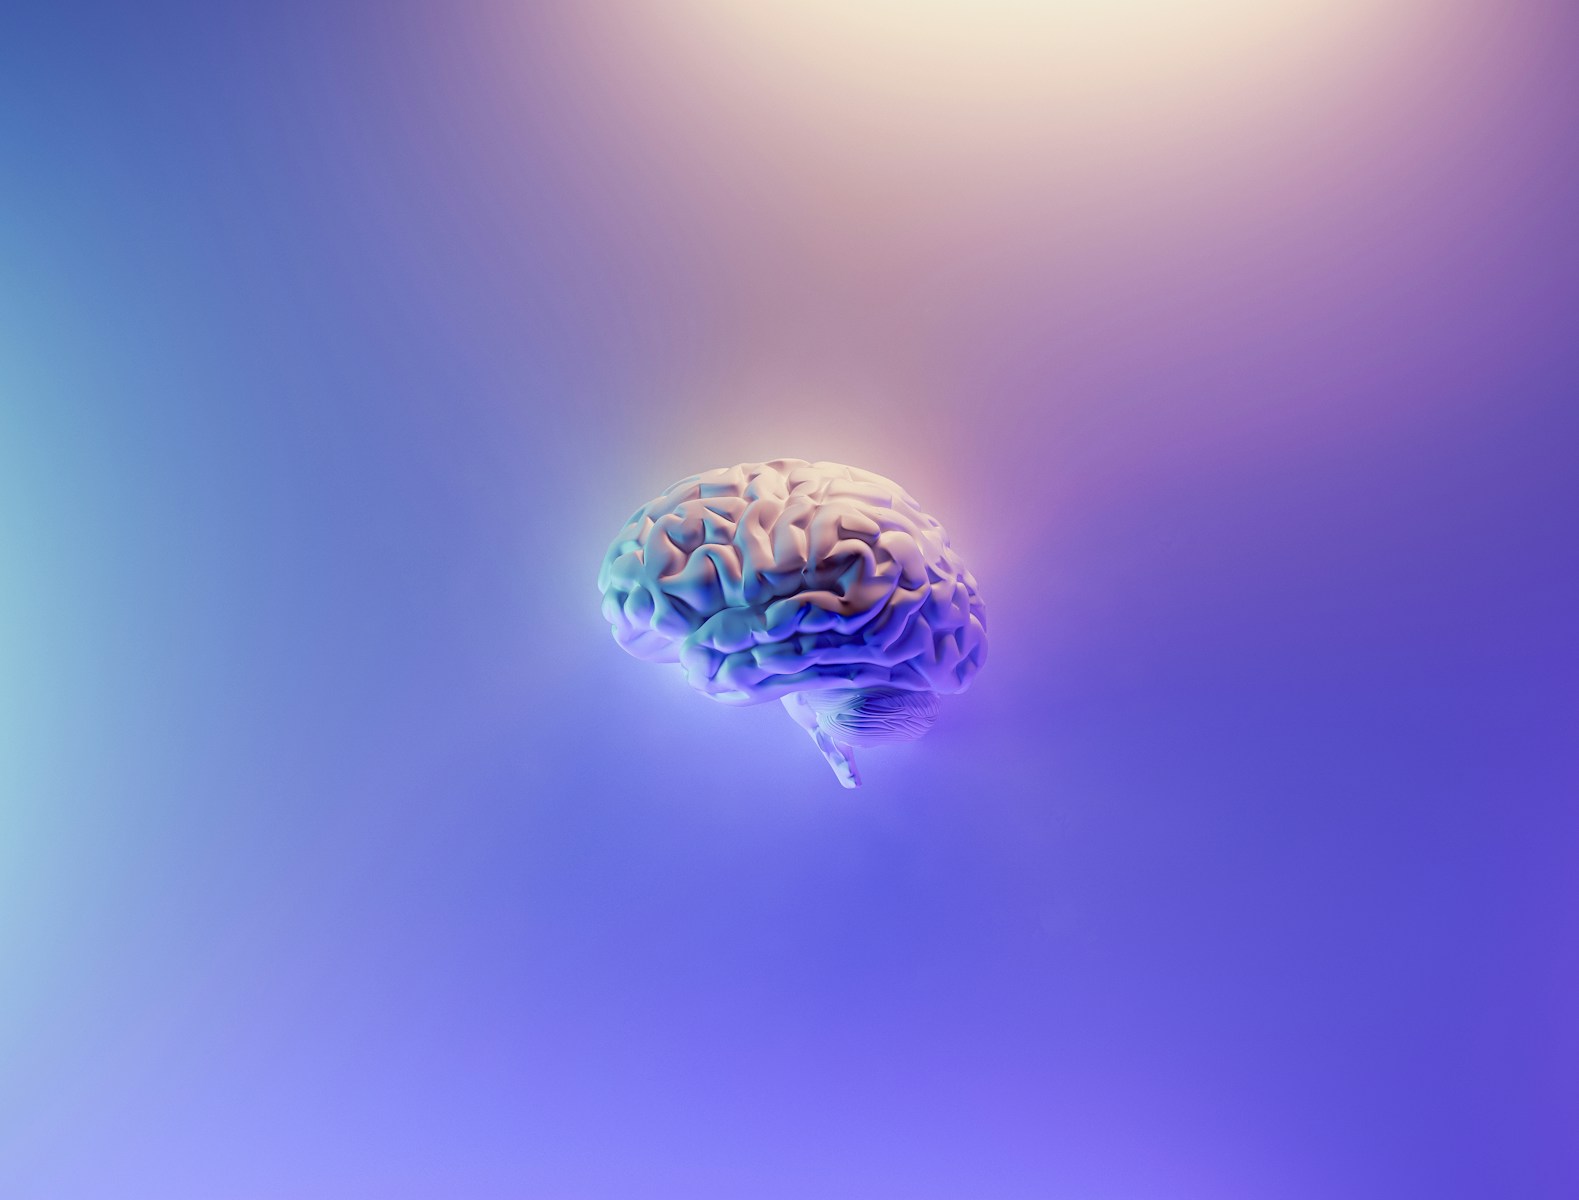

Vo svete medicíny sa pripravuje fascinujúci zvrat. Vedci totiž skúmajú schopnosti známeho parazita Toxoplasma gondii. Tento mikroorganizmus sa údajne skrýva v každom treťom človeku na svete a nenápadne sa usídľuje v mozgu a rôznych orgánoch. Výskumníci teraz využívajú tento jeho skrytý potenciál, aby vyvinuli novú metódu na dodávanie liekov priamo do mozgu.

Dodávanie liekov do mozgu je známe kvôli ochrannej bariére známej ako hematoencefalická bariéra (BBB). Táto zložitá membrána umožňuje prenikanie len určitých látok z krvného obehu do mozgového tkaniva. Je obzvlášť odolná voči väčším molekulám, čo komplikuje dodávanie liekov.

Zaujímavé je, že parazit túto mozgovú „pevnosť“ zrejme ľahko obchádza. Keď sa usídli napríklad v mozgu myší, zmení ich správanie a v prítomnosti mačiek sa stanú nebojácnymi. Človek ho môže požiť a dostane sa do mozgu, pričom u väčšiny ľudí často nespôsobí viditeľné poškodenie. Je však dôležité si uvedomiť, že u malého percenta sa môžu vyskytnúť nepriaznivé účinky (napr. hyperaktivita, zápal mozgu a ďalšie).

V prelomovej štúdii v časopise Nature Microbiology vedci vytvorili parazita tak, aby fungoval ako kuriér liekov. Tento inovatívny prístup umožňuje parazitovi prepravovať rôzne náklady (napr. proteíny) priamo do mozgových buniek a následne ich uvoľňovať.

Premena parazita na účinný prostriedok dodávania liekov si vyžadovala roky výskumu. Vedci využili dve kľúčové štruktúry v rámci parazita. Roptrie, ktoré vstrekujú proteíny do hostiteľských buniek zvonka, a husté granule, ktoré vylučujú proteíny zvnútra. Tento dvojitý mechanizmus umožňuje efektívnejšie cielené doručovanie menších proteínov aj väčších proteínových náloží. Vedci sa domnievajú, že po väčšom zdokonalení by tieto doručovacie systémy mohli slúžiť na rôzne terapeutické účely.

Pri testoch na myšiach upravené parazity nevyvolali ochorenie. Je však dôležité poznamenať, že môžu byť škodlivé, najmä pre osoby s oslabeným imunitným systémom. V takýchto prípadoch sa parazit môže nekontrolovane množiť a potenciálne poškodiť mozog, srdce a oči. Okrem toho predstavuje riziko pre vyvíjajúce sa plody s možnými vážnymi následkami, ako je slepota alebo mozgová dysfunkcia. Tento nový spôsob transportu bude vyžadovať zabezpečenie čo najväčšej neškodnosti parazita, aby sa pripravila pôda pre budúce používanie. Výskumy sú však stále v štádiu testovania (nie na ľuďoch), preto si na podrobnejšie informácie budeme musieť počkať.